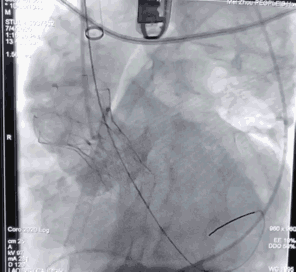

3228-200胸主动脉支架定位

胸主动脉支架释放后造影

由于患者年龄较大,主动脉严重缩窄合并主动脉瘤,主动脉结构较为脆弱,所以李存仁教授决定在胸主动脉覆膜支架植入后再对缩窄部位进行球扩。这样,已经植入的支架能够起到一定的保护作用,在支架的限制下,球囊既充分扩开了狭窄部位,又避免了过度扩张对主动脉造成的损伤。

使用球囊28mm*40mm扩张

植入弹簧圈进行填充封堵内漏